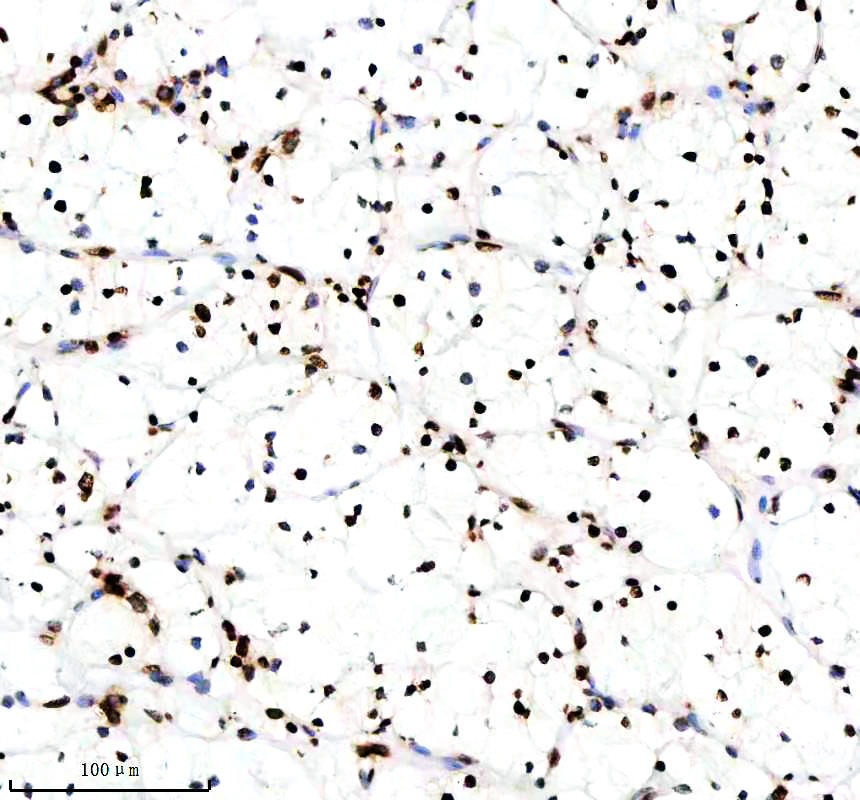

IHC analysis of Histone H3 (acetyl K14) using anti-Histone H3 (acetyl K14) antibody (BM4151) .

Histone H3 (acetyl K14) was detected in a paraffin-embedded section of human clear cell renal cell carcinoma tissue. The tissue section was incubated with rabbit anti-Histone H3 (acetyl K14) Antibody (BM4151) at a dilution of 1:200 and developed using HRP Conjugated Rabbit IgG Super Vision Assay Kit (Catalog # SV0002) with DAB (Catalog # AR1027) as the chromogen.

IHC analysis of Histone H3 (acetyl K14) using anti-Histone H3 (acetyl K14) antibody (BM4151) .

Histone H3 (acetyl K14) was detected in a paraffin-embedded section of human clear cell renal cell carcinoma tissue. The tissue section was incubated with rabbit anti-Histone H3 (acetyl K14) Antibody (BM4151) at a dilution of 1:200 and developed using HRP Conjugated Rabbit IgG Super Vision Assay Kit (Catalog # SV0002) with DAB (Catalog # AR1027) as the chromogen.